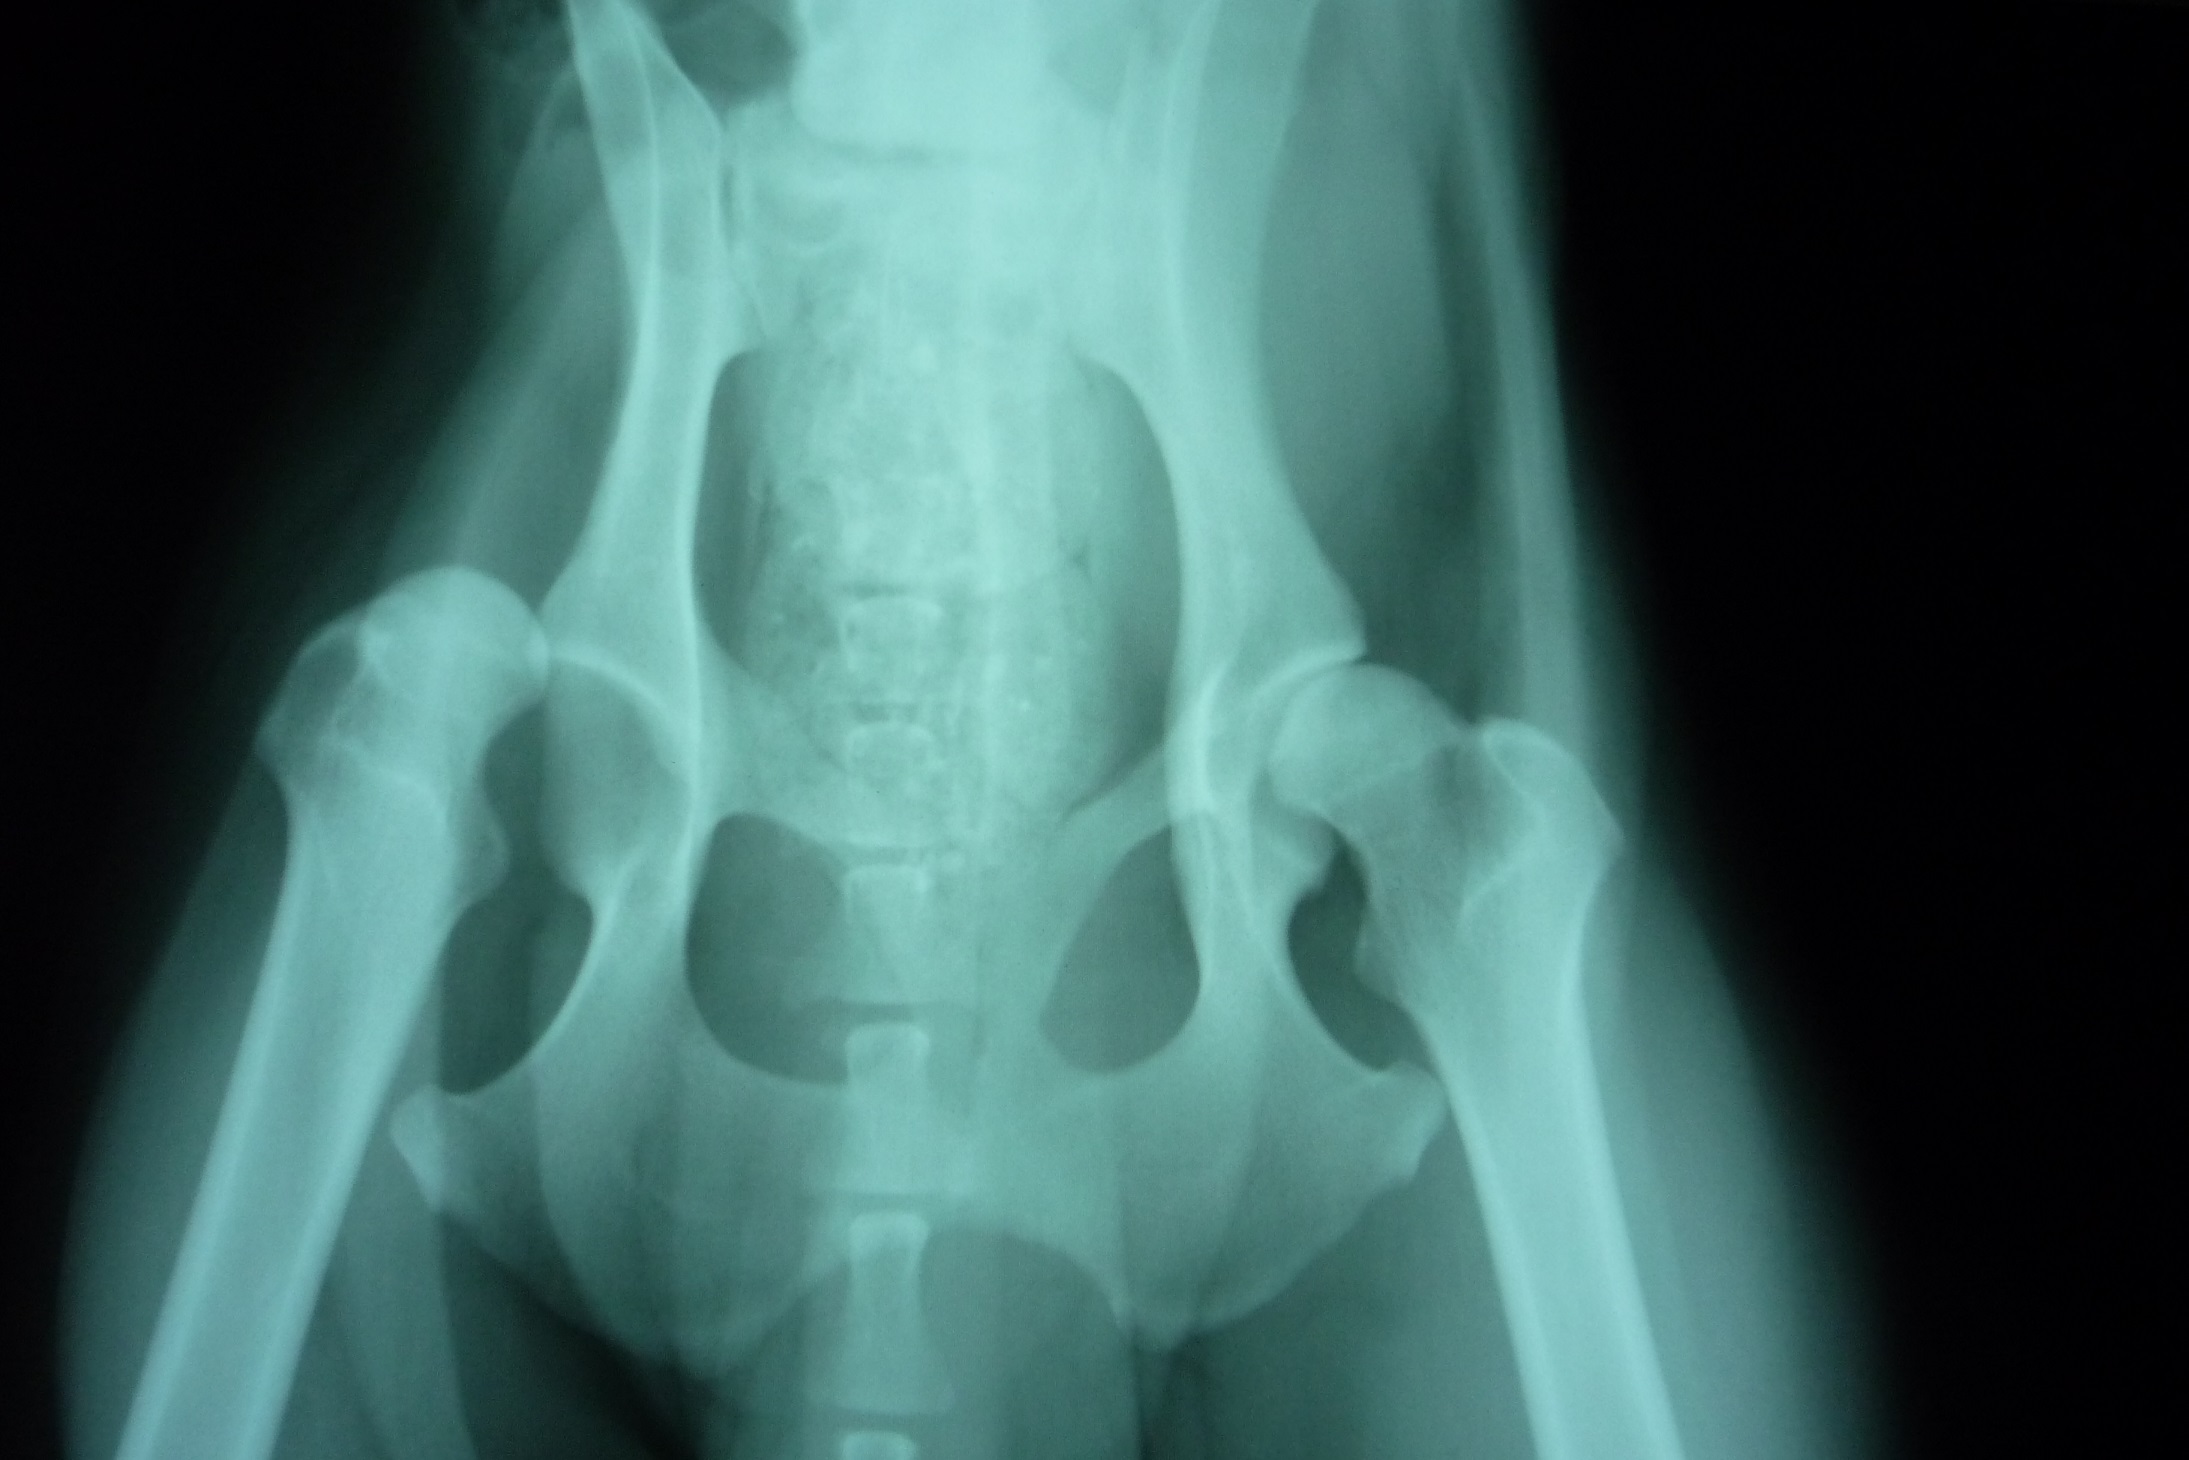

Notre bénévole a donc récupéré le pauvre loulou, consultation vétérinaire, radio : luxation de la tête du col du fémur mais comme souvent dans ces cas-là, la manipulation n’est plus suffisante car la luxation est trop ancienne, la chirurgie est indispensable (résection de la tête du fémur).